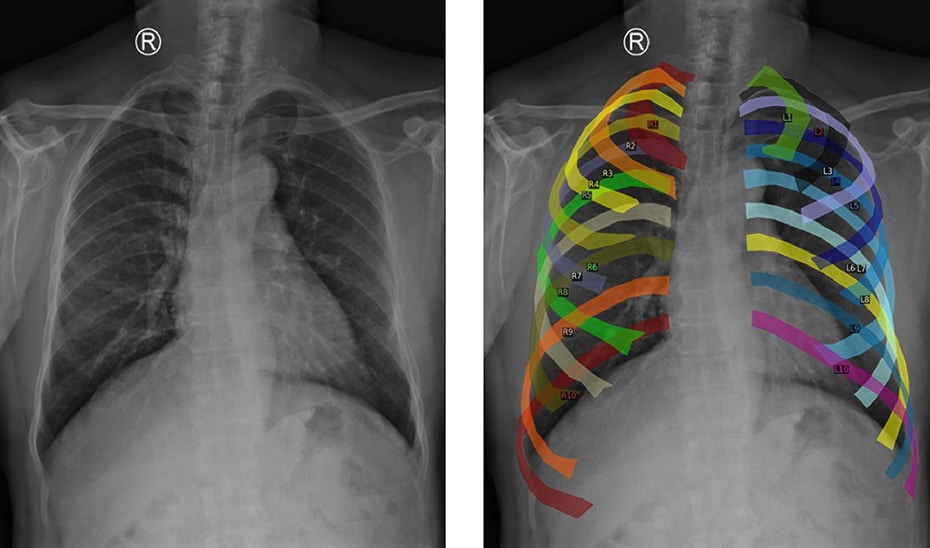

La importancia de este avance radica en su capacidad para identificar anomalías que, como en el caso de patologías como la silicosis, pueden presentar síntomas sutiles en las etapas iniciales. Estos síntomas, difíciles de detectar, pueden dar lugar a diferentes interpretaciones clínicas. Según el estudio publicado en la revista Expert Systems with Applications, el modelo Mamba-YOLOvX permite localizar de manera eficaz lesiones de diversos tamaños mediante algoritmos de aprendizaje automático y arquitecturas de redes neuronales convolucionales. Este enfoque imita el funcionamiento de la corteza visual humana, permitiendo al sistema aprender y mejorar en la identificación de patrones y características complejas a partir de miles de imágenes.

Este nuevo modelo combina información global de la imagen, como la forma de los pulmones o la posición del corazón, con información local, permitiendo identificar anomalías a diferentes escalas. Incorpora también mecanismos de atención espacial y de canal que se centran en las áreas relevantes de la radiografía, discriminando zonas que no aportan información útil.

Para mejorar el entrenamiento del modelo, se utilizaron datos de distintos centros hospitalarios y una técnica conocida como aumento de datos, que genera nuevas imágenes homogéneas desde una perspectiva anatómica. Esto garantiza que el modelo sea robusto y funcione eficazmente, incluso ante variaciones en las radiografías de distintos hospitales.